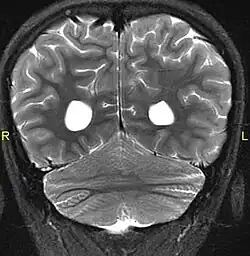

Aside from the physical characteristics of the eyes there is also less sensation in the eyes when stimulated.[4] The eyes also show low motor control (ataxia).[4] Along with ataxia comes a lack of coordination or ability to judge the distance of objects (dysmetria).[6] MRIs show a constant feature of rhombencephalosynapsis–a condition marked by the absence or partial absence of the cerebellar vermis and varying degrees of fusion in the cerebellum in every case of Gómez–López-Hernández syndrome.[4][7][8] Also absent are the trigeminal nerve of the trigeminal cave and the foramen rotundum, causing abnormal sensations on the forehead and the corneas.[6][8] One Gómez–López-Hernández syndrome case in Japan also presents fever-induced seizures.[9] Others may or may not present with non-fever-induced seizures.[4] Malformations of motor centers in the brain cause reduced muscle strength (hypotonia).[8] Eleven of fifteen people in one study showed moderate-to-severe intellectual disability.[6] In cases where it has been noted, head nodding is present.[6] Hydrocephalus and enlargement of the ventricular system is consistently present.[6] A reduced corpus callosum is present in some cases (agenesis of the corpus callosum).[6]